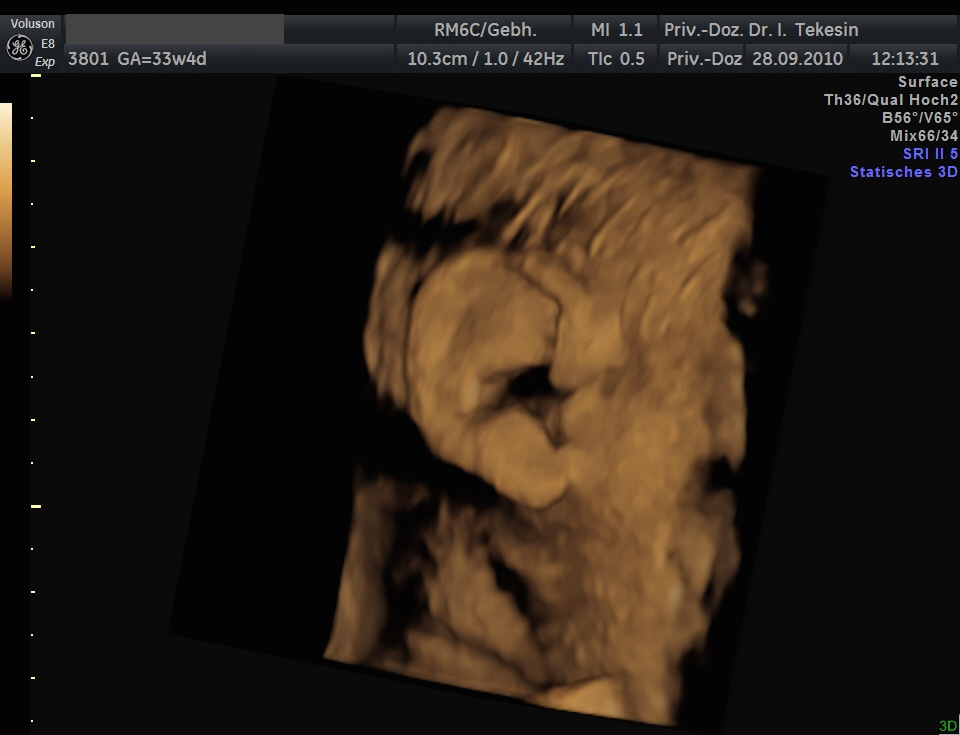

3D-/4D-Ultraschall (optional)

Immer mehr werdende Eltern interessieren sich für die faszinierenden Bilder, die dieses Verfahren liefert. Die plastische, dreidimensionale Darstellung der Oberfläche des Gesichts und anderer Körperregionen wird durch spezielle Bildrekonstruktion in schnellen Rechnern erreicht. Auch einzelne innere Organe oder „Gefäßbäume“ können von allen Seiten betrachtet werden. Viele dünne Schnittebenen (2D) werden zu einer gemeinsamen 3D-Sichtweise im Computer des Ultraschallgerätes zusammengeführt. Unter einem 4D-Ultraschall versteht man darüber hinaus eine 3D-Ultraschalluntersuchung unter Echtzeitbedingungen. Anstatt nur statische Bilder anzuzeigen, erfasst ein 4D-Ultraschall die Bewegungen des Kindes, weshalb er auch als „Live-3D-Ultraschall“ bezeichnet wird.

Diese Vorgehensweise ermöglicht äußerst realistische Bilder, bei denen sogar Gestik und Mimik des Kindes in bewegten Sequenzen festgehalten werden können. Die Untersuchung kann wie auch der normale Ultraschall während des gesamten Schwangerschaftszeitraums durchgeführt werden. Möchte man das Ungeborene komplett sehen, wird die 12. bis 16. Schwangerschaftswoche empfohlen, die Zeit zwischen der 28. und 33. Schwangerschaftswoche eignet sich besonders zur präzisen Darstellung einzelner Körperteile

Wir sehen in diesem modernen Verfahren in erster Linie eine ergänzende Maßnahme bei speziellen Fragestellungen bezüglich Herz, Gehirn oder Skelett und vor allem bei Verdacht auf eine fetale Besonderheit.

Ohr und Haare in der 34. Woche (3D-Darstellung)